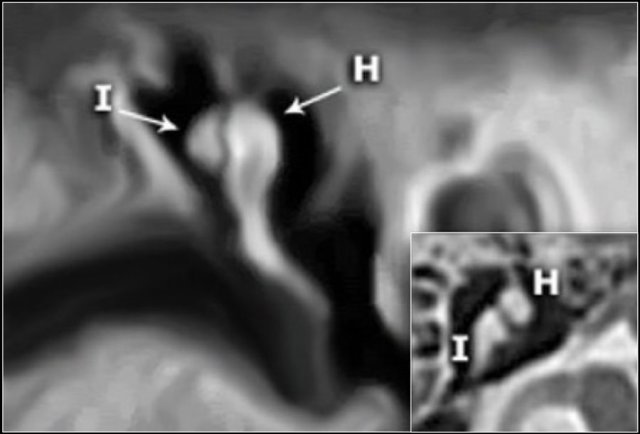

Ossicles

In many illustrations you will see the incus connecting medially to the malleus, but this is not correct.

On the coronal reconstruction on the left it is clearly demonstated that the incus is positioned posterolaterally to the malleolar head.

The long crus of the incus subsequently runs inferomedially to the stapes.